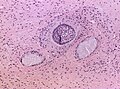

Features (adamantinomatous):[6]

- Trabecular squamous epithelium bordered by palisaded columnar epithelum.

- Lobules with loosely distributed epithelia ("stellate reticulum").

- Well-circumscribed (or pseudoinvasive border).

- Multicystic.

- Small-to-medium sized cells with moderate amount of basophilic cytoplasm.

- Bland nuclei (with occ. small nucleoli).

- "Wet" keratin - nests of whorled keratin.

- Calcifications (non-psammomatous).